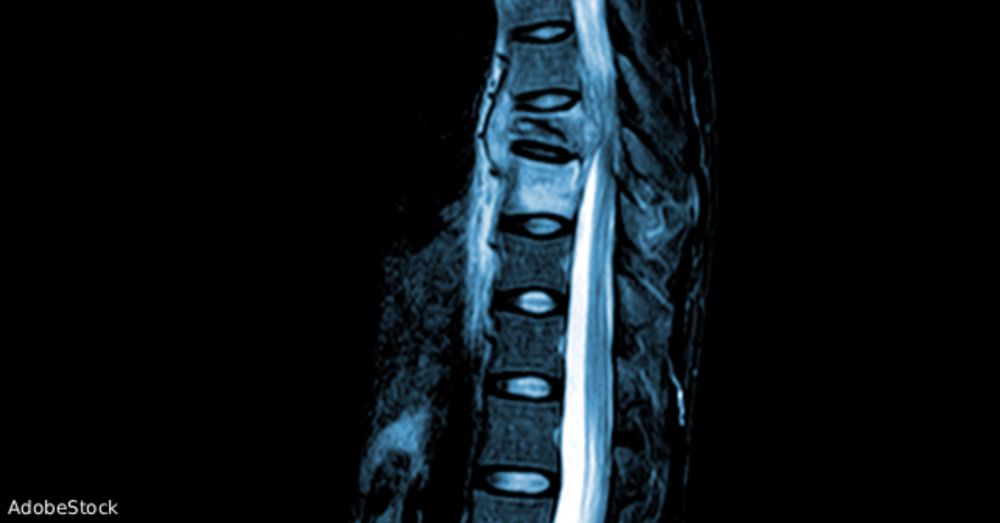

The question was posed: can ESR and CRP contribute useful diagnostic information for the evaluation of spinal epidural abscess?

My take in @acepnation.bsky.social ACEPNow!

(hint: nope!) #medsky

www.acepnow.com/article/is-t...

Is There Any Way Out for Spinal Epidural Abscess? - ACEP Now

Can ESR & CRP reliably rule out acute infectious spinal pathology? A new study explores using these markers to avoid MRI for spinal epidural abscess.

www.acepnow.com